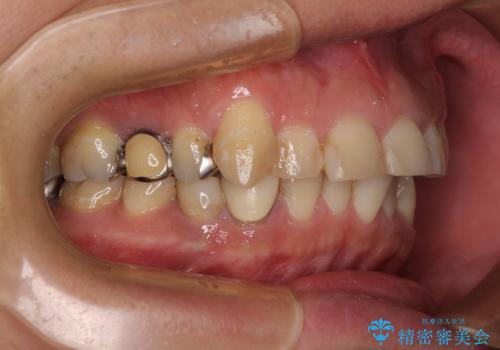

- 近医にて下顎奥歯の抜歯が必要と言われたとのことで来院された患者様です。

診察の結果、奥歯は左右ともに抜歯が必要な状態でした。

他の銀歯も気になっており、セラミックにしたいとの要望があり、詳しくお話をすると、デコボコの歯ならびも整えたいとのことでした。

抜歯が必要な歯は事前に抜歯をし、その後ワイヤー装置にて歯列矯正を行い、途中でインプラントを埋入し、オールセラミッククラウンにて補綴治療を行うこととしました。